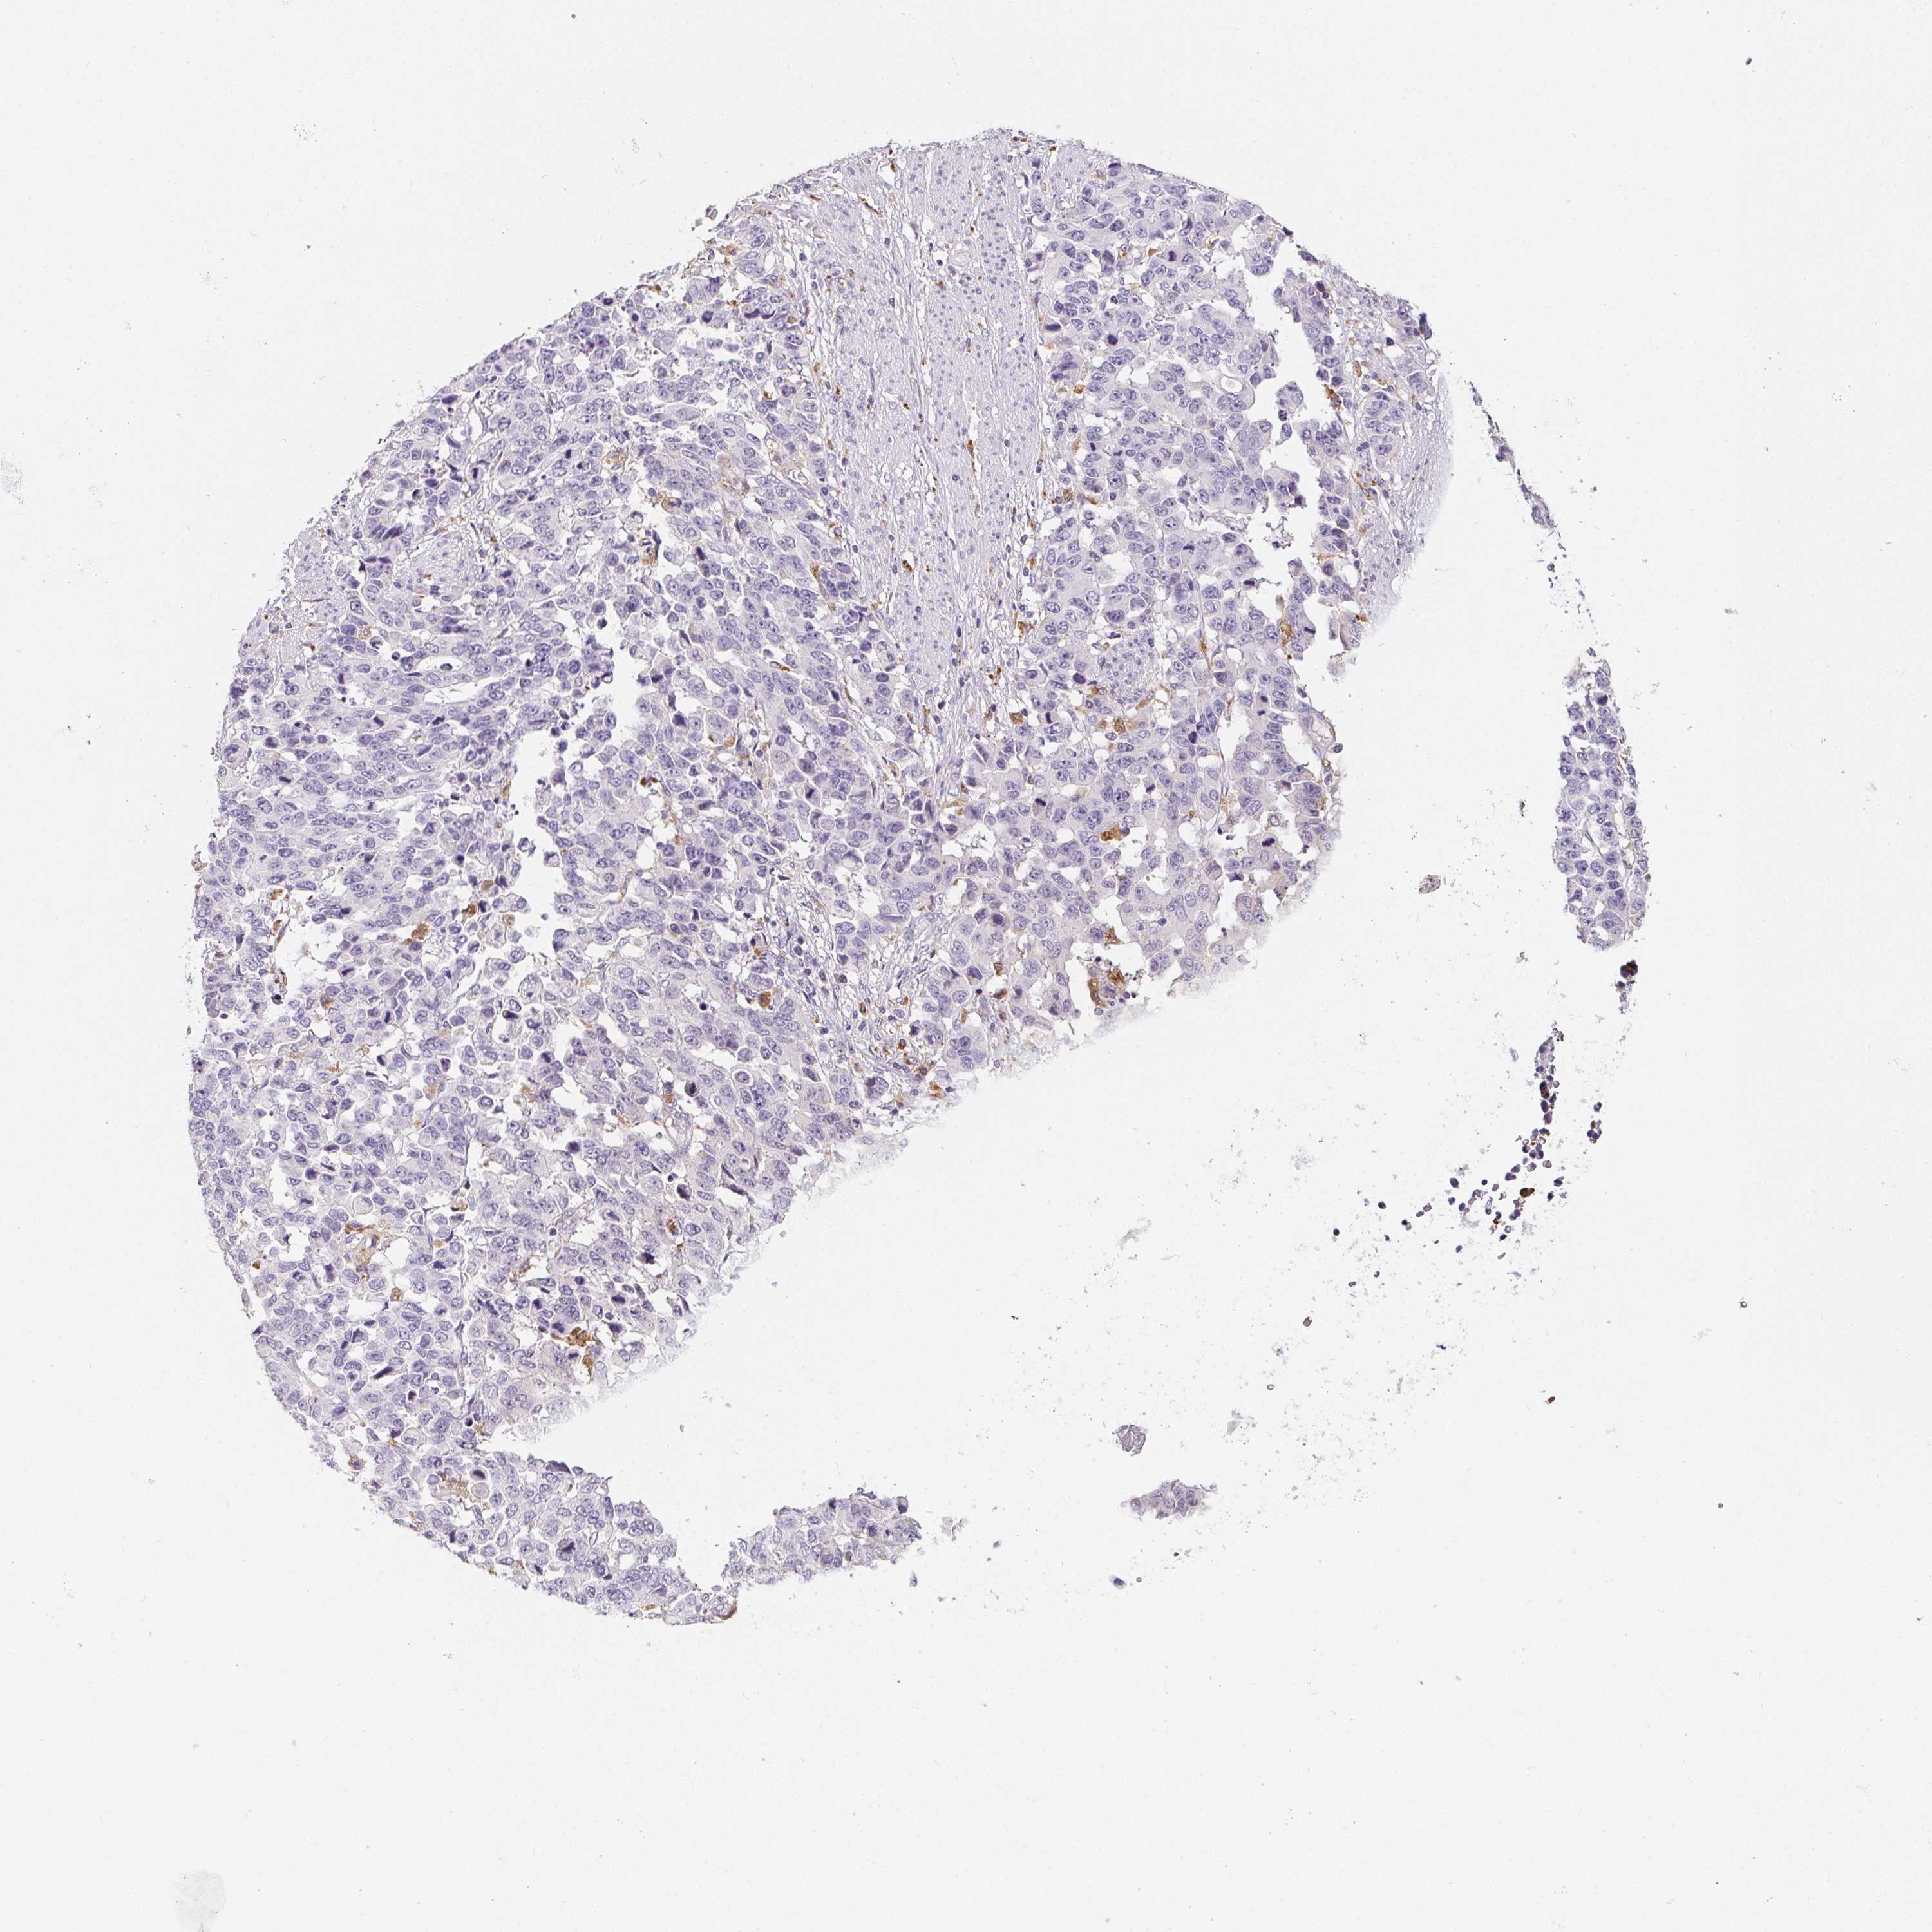

STOMACH CANCER - Protein expressioni

A mouse-over function shows sample information and annotation data. Click on an image to view it in a full screen mode. Samples can be filtered based on level of antibody staining by selecting one or several of the following categories: high, medium, low and not detected. The assay and annotation is described here.

Note that samples used for immunohistochemistry by the Human Protein Atlas do not correspond to samples in the TCGA dataset.

Antibody stainingi

Antibody staining in the annotated cell types in the current human tissue is reported as not detected, low, medium, or high, based on conventional immunohistochemistry profiling in selected tissues. This score is based on the combination of the staining intensity and fraction of stained cells.

Each image is clickable and will lead to virtual microscopy that enables deeper exploration of all samples and also displays staining intensity scores, fraction scores and subcellular localization as well as patient and tissue information for each sample.

Antibody HPA057052

Antibody CAB034892

Staining

High

Medium

Low

Not detected

Intensity

Strong

Moderate

Weak

Negative

Quantity

>75%

75%-25%

<25%

None

Location

Nuclear

Cytoplasmic/membranous

Cytoplasmic/membranous,nuclear

Adenocarcinoma, NOS